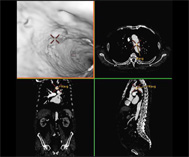

冠動脈CT

CTの登場により画像診断は飛躍的に向上しましたが、近年マルチスライスCT(MDCT)が開発されたことで空間分解能に優れた高精細な画像が極めて短時間で得られるようになり、画像診断はさらに進化しました。

CT画像を用いた3次元画像は今でこそ多くの施設で活用されるようになりましたが、その開発に当放射線科は深く関ってきました。現在では、大動脈瘤や大動脈解離などの大血管疾患や閉塞性動脈硬化症などの末梢血管疾患に加え心臓の冠動脈の3次元画像も提供できるようになり、これまで血管造影でしか得られなかった情報をおよそ10分程度の外来検査で正確に知ることができるようになりました。また、早期脳梗塞の診断において注目されているCT perfusion(CT灌流画像)も海外の大学と共同で開発し国内外での普及に努めてきました。これらの成果は欧州放射線学会から金賞ならびに銀賞を授与され、また日本医学放射線学会でも金賞を受賞し、広く国内外で認められています。